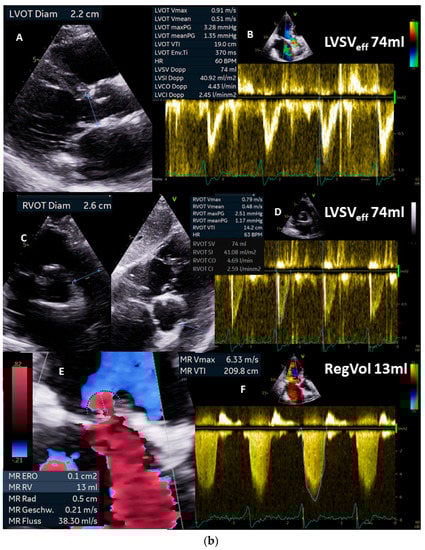

Figure 3.

(a): Illustration of underestimation of LVEDV and LVESV by 2D echocardiography: in (A), the planimetry of LVEDV in the two-chamber view (2-ChV) is shown; in (B), the corresponding LVESV is shown. In (C), the planimetry of LVEDV in the four-chamber view (4-ChV) is shown; in (D), the corresponding LVESV is shown. However, the obvious difference between the longitudinal LV axis in the 4-ChV between diastole and systole indicates the foreshortening of the 4-ChV causing errors of LV volume assessment. LVSV = left ventricular stroke volume, LVSVtot = total LVSV, LVSVeff = effective LVSV, LVEDV = left ventricular end diastolic volume, and LVESV = left ventricular end systolic volume. (b): Measurements of the corresponding LVEDV areas in adjusted sectional planes by postprocessing in a 3D dataset in comparison with the 2D echocardiography presented in (a): in (A), the LVEDV assessment of the adjusted four-chamber view is shown; in (B), the perpendicular lines of the apical planes in the short-axis view of the 3D dataset are shown; in (C), the 3D view of the azimuth plane is shown; in (D), the LVEDV assessment of the adjusted two-chamber view is shown. In (E), a parasternal short-axis view during systole to label the RVOT is shown. In (F), the RVOT-pw-Doppler spectrum is shown. In (G), a parasternal long-axis view during systole to label the LVOT is shown. In (H), the LVOT-pw-Doppler spectrum is shown. Estimation of effective LVSV is performed with pw Doppler echocardiography by determination of forward RVSV. In isolated mitral regurgitation, a countercheck can be performed by assessment of forward LVSV which corresponds to forward RVSV. LVSV = left ventricular stroke volume, RVSV = right ventricular stroke volume, LVSVtot = total LVSV, LVSVeff = effective LVSV, LVEDV = left ventricular end-diastolic volume, RVOT = right ventricular outflow tract, and LVOT = left ventricular outflow tract.